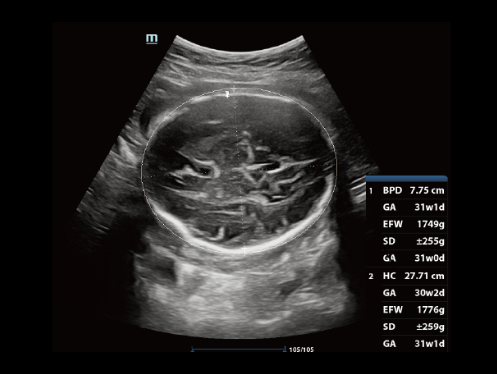

ImГЎgenes ClГӯnicas